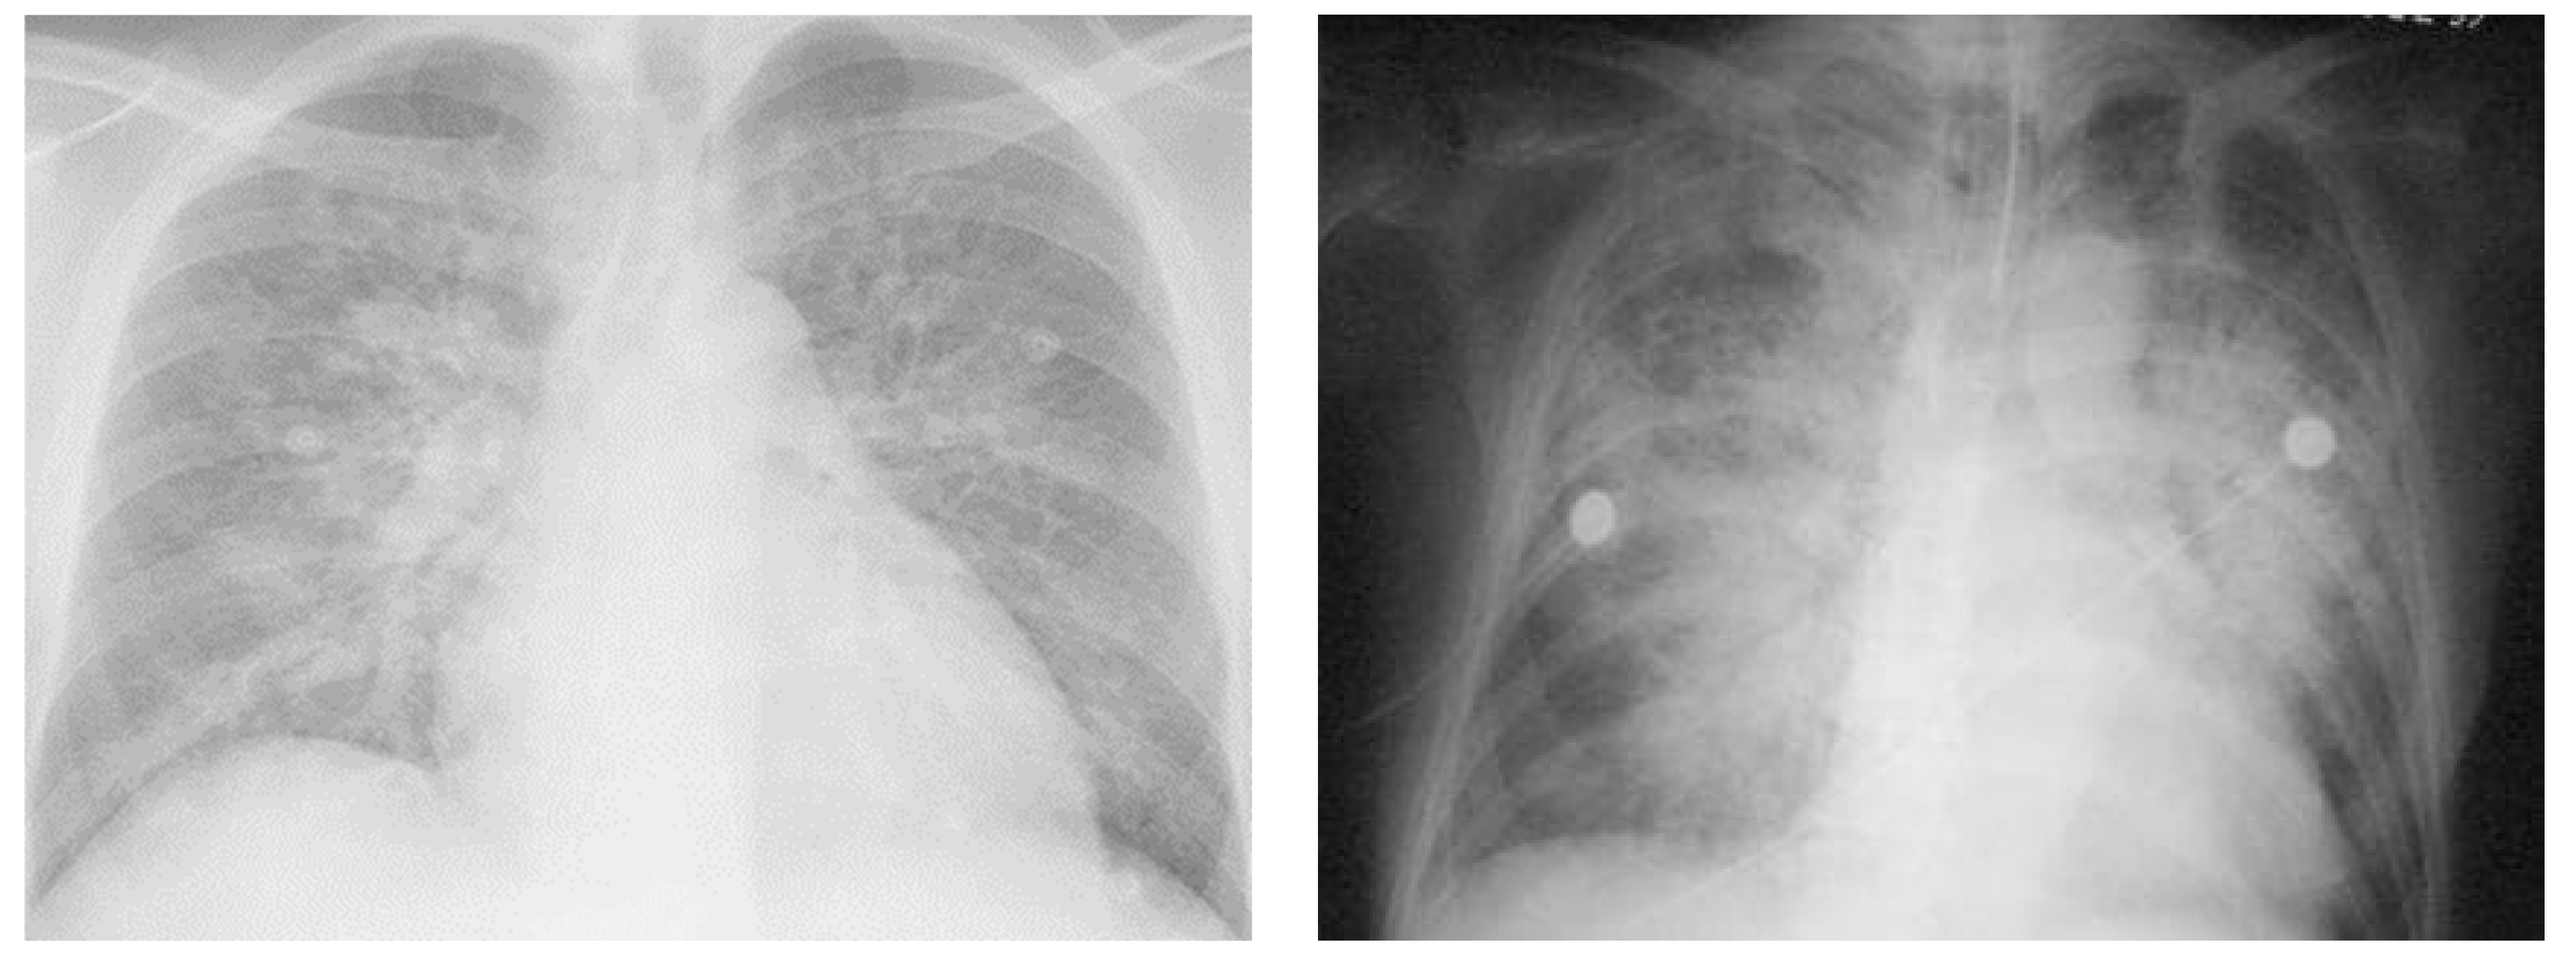

Chest radiography is one of the most important investigations required for the evaluation of pulmonary edema and can help distinguish between CPE and NCPE [36,38,39]. However, the characteristic features (Table 4 and Figure 3) described in chest X-rays have only moderate specificity (75–83%) and poor sensitivity (50–68%) in the diagnosis of CPE [38].

Figure 3.

Chest Radiographs representing Cardiogenic and Noncardiogenic Pulmonary Edema. Left X-ray shows an anteroposterior chest Rx with acute anterior myocardial infarction and acute cardiogenic pulmonary edema. Signs of cardiogenic pulmonary edema are peri broncho vascular spaces and the prominent septal lines (Kerleyșs B lines). Right X-ray shows an anteroposterior chest Rx with noncardiogenic pulmonary edema, with blood culture positive for Streptococcus pneumoniae, causing pneumonia complicated by septic shock and acute respiratory distress syndrome. Diffuse alveolar infiltrates appear patchy and bilateral with air bronchograms, findings that are charac-teristics of, but not specific to, noncardiogenic edema and acute lung injury.